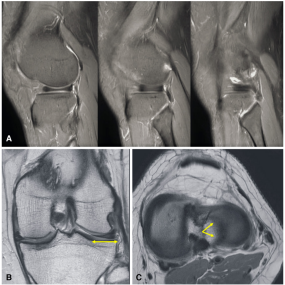

盘状半月板的MRI诊断方法

图片来源:doi:10.1136/jisakos-2017-000162.

MRI诊断方法:

(A)质子密度脂肪饱和序列中,连续3个5mm厚的矢状面前后角相连。

(B) T2加权冠状面外侧半月板宽度为胫骨总宽度的20%(黄色箭头)。

(C)半月板轴位片显示外侧半月板明显的盘状形态(黄色箭头),覆盖胫骨外侧平台的>80%。